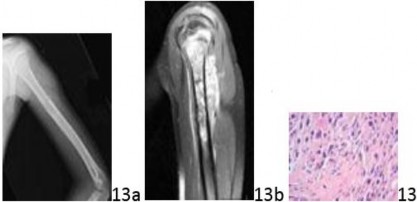

Question 13 A 9-year-old boy with a history of unilateral retinoblastoma has a 2-week history of left arm pain. His mother, who had bilateral retinoblastoma, noted a mass on his left proximal arm 2 days prior to the office visit. A radiograph, MRI scan, and biopsy specimen are seen in Figures 13a through 13c. What is the most appropriate treatment?

DISCUSSION: The radiograph and MRI scan show an aggressive lesion in the left proximal humerus in a child with a history of retinoblastoma. The biopsy specimen shows pleomorphic spindled cells with focal osteoid. There is a well-documented association between retinoblastoma and osteosarcoma because it has been found that most, if not all, such tumors have defects in their RB1 pathway through genetic lesions in the RB1 gene itself or other genes in the pathway. Linkage analysis at the retinoblastoma gene (RB1) locus is required for identification of individuals at risk of developing retinoblastoma and osteosarcoma. Identification of disease-causing mutations is necessary for accurate risk prediction. The treatment for osteosarcoma is chemotherapy and surgery, either wide local resection or amputation.

Radiotherapy is not a useful adjunct in the treatment of osteosarcoma. Chemotherapy and wide resection is the preferred treatment. The Preferred Response to Question # 13 is 4.

Question 13 A 9-year-old boy with a history of unilateral retinoblastoma has a 2-week history of left arm pain. His mother, who had bilateral retinoblastoma, noted a mass on his left proximal arm 2 days prior to the office visit. A radiograph, MRI scan, and biopsy specimen are seen in Figures 13a through 13c. What is the most appropriate treatment?

DISCUSSION: The radiograph and MRI scan show an aggressive lesion in the left proximal humerus in a child with a history of retinoblastoma. The biopsy specimen shows pleomorphic spindled cells with focal osteoid. There is a well-documented association between retinoblastoma and osteosarcoma because it has been found that most, if not all, such tumors have defects in their RB1 pathway through genetic lesions in the RB1 gene itself or other genes in the pathway. Linkage analysis at the retinoblastoma gene (RB1) locus is required for identification of individuals at risk of developing retinoblastoma and osteosarcoma. Identification of disease-causing mutations is necessary for accurate risk prediction. The treatment for osteosarcoma is chemotherapy and surgery, either wide local resection or amputation.

Radiotherapy is not a useful adjunct in the treatment of osteosarcoma. Chemotherapy and wide resection is the preferred treatment. The Preferred Response to Question # 13 is 4.